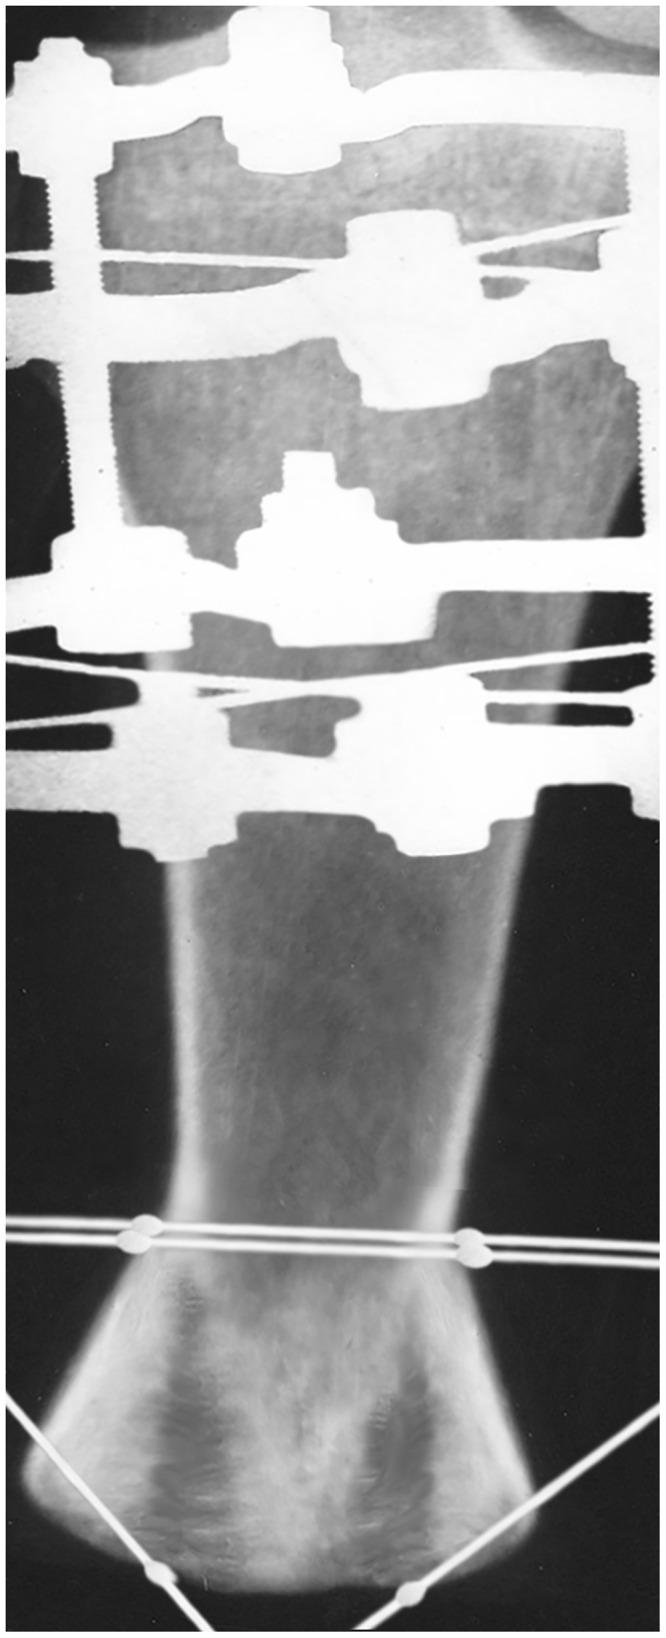

The formation of a functional tibial stump after combat injuries with extensive tissue damage is sometimes difficult. We describe a case of reconstruction of the tibial stump after a mine-blast injury. In this case, the fibula was completely removed as a result of fracture, and the tibia was amputated at the border of the upper and middle thirds. To create a stable platform with a larger bearing surface area and reduce the load on the distal fossa, the Ilizarov method was used. For the first time, the area of the bearing surface of the tibia stump was increased by more than 2 times in the case of the removed fibula. Thanks to the original surgery technique, the mushroom shape of the stump end was also obtained for the first time. In the process of prosthetics, this geometry actually increases the bearing surface area and has advantages over the Ertl technique, where the cylindrical end of the stump due to muscle atrophy and thinning of the fibro-skin lining can lead to bursitis and even ulcers. The spherical shape of the stump end causes less soft tissue trauma, increases the load-bearing capacity and durability of the results. According to the data of the GaitRite system, the walking performance in the long-term period practically corresponded to that of a healthy person. The technique of the operation is described in detail, including petal decortication, two oblique corticotomies of the tibia, formation of bone and periosteum fragments, distraction. The result is a highly functional stump with the possibility of using end support and full prosthetics. The proposed technique can be used in reconstructive operations on the tibia and femur stumps.